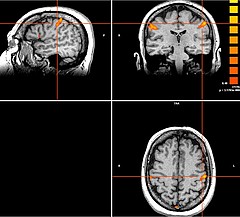

Tiefe Hirnstimulation

Bei bestimmten Bewegungsstörungen, die nicht oder nicht mehr ausreichend auf eine medikamentöse Therapie ansprechen, ist es möglich, die hierfür verantwortlichen Hirnareale durch die sog. Tiefe Hirnstimulation zu beeinflussen. Hierbei werden feine Elektroden in das Gehirn eingesetzt, um fehlerhafte Nervenstrukturen mit elektrischen Impulsen zu aktivieren oder zu hemmen. Beim Morbus Parkinson, dem essentiellen Tremor oder der Dystonie sind beispielsweise spezifische Hirnareale überaktiv, die dann gezielt durch die Tiefe Hirnstimulation gehemmt und die Symptome wie Zittern oder Muskelsteifigkeit dadurch unterdrückt werden können. Die Hirnregionen selbst bleiben dabei intakt, sodass die Stimulation jederzeit rückgängig gemacht werden kann. Die elektrische Stimulation wird durch einen Impulsgeber gesteuert, der ähnlich wie ein Herzschrittmacher unter die Haut an der Brust der Patient:innen implantiert wird. Die Einstellungen des Impulsgebers lassen sich von außen jederzeit verstellen, sodass die Stimulation an veränderte Bedürfnisse der Patient:innen stets angepasst werden kann.